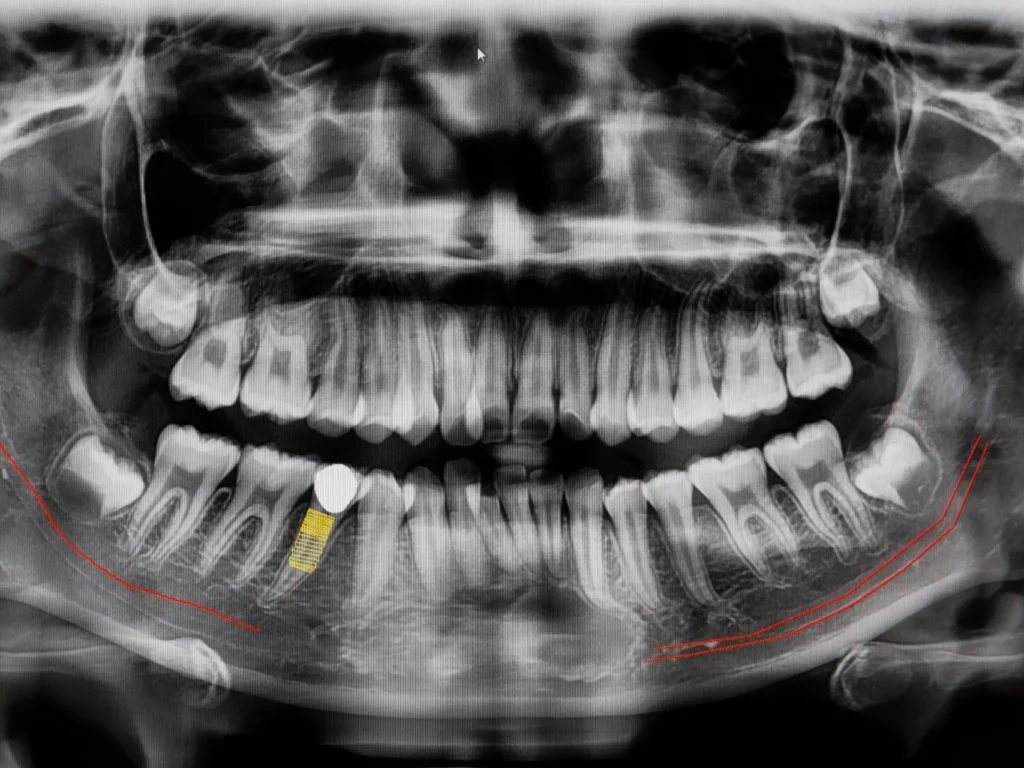

CBCT stands for ConeBeam Computed Tomography, which is a special type of digital x-ray scanner that dentists use to see a 3D image of your mouth and teeth.

The ConeBeam CT imaging system rotates once around your head while you stand or sit in a chair. The process is quick, simple, and completely painless. We use these scans to provide the best treatment in dental implants, root canals, diagnosis of dental and facial pain, etc.

We can evaluate your teeth and facial structures from literally every angle, in 3D, and in color! Routine x-rays, on the other hand, produce a single flat image with limited information.

You can have absolute confidence and satisfaction in the treatment you receive, knowing we’ve analyzed every problem with 3D technology.

Digital sensors capture detailed x-ray images with a fraction of the exposure found in traditional film x-rays. Technological advancements in x-ray technology provide multiple benefits:

Safety | Our digital x-ray system provides up to 90% reduction in radiation compared to older film-based systems.

Time Savings | Images captured instantly with a digital sensor lessen the time you spend in the dental chair.

Better Outcomes | Improved image clarity increases our ability to diagnose and treat conditions.